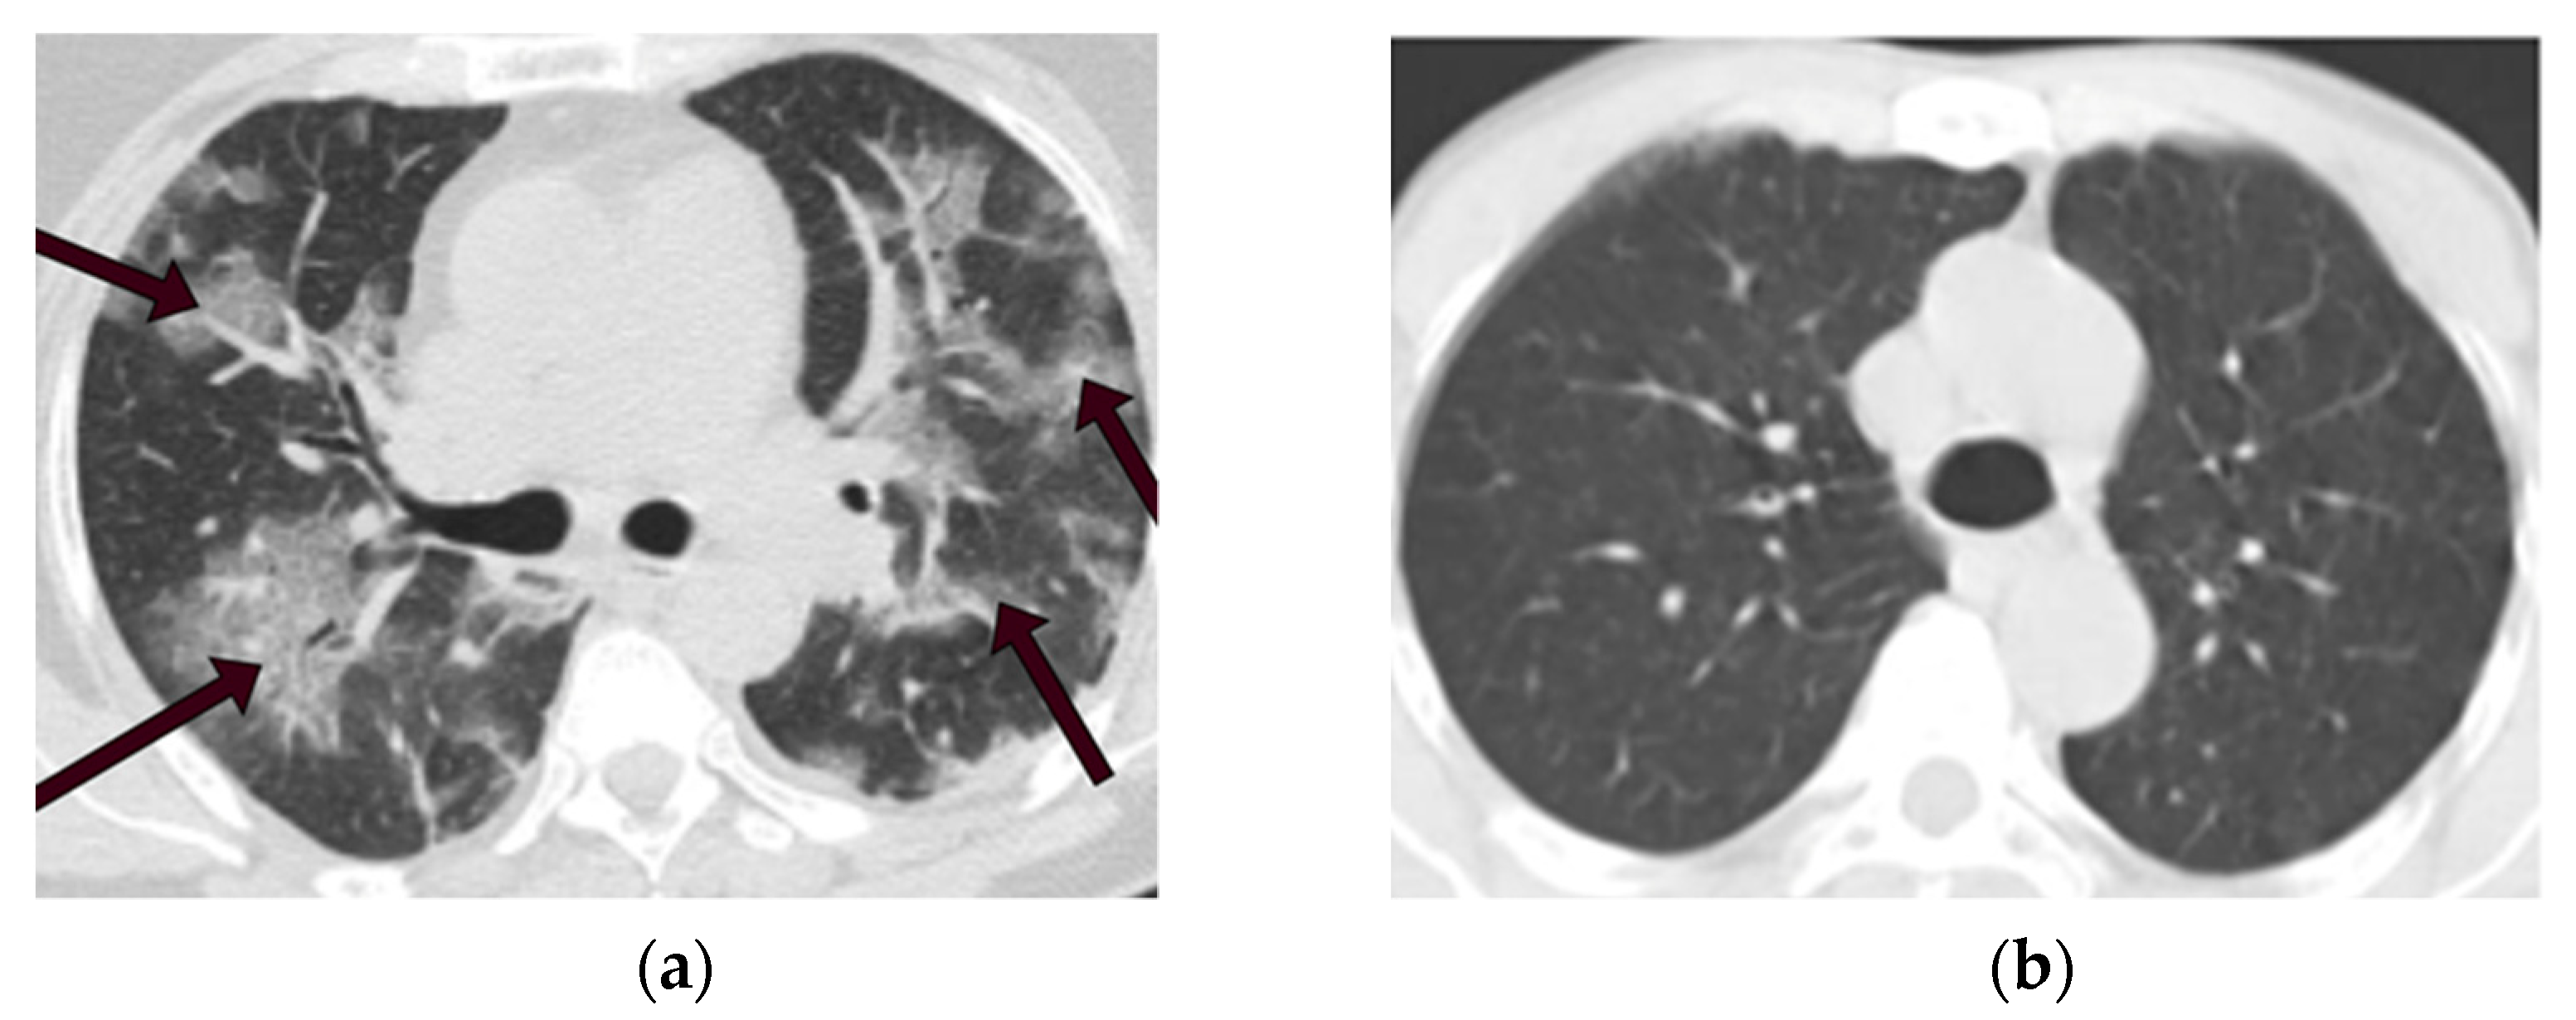

These CT scan images are in PNG format with 104 × 119 to 416 × 512 spatial resolution. We selected 1229 images from each category to make the data balanced perfectly. Figure 2a displays a CT scan of a COVID-19 patient in this dataset, the area indicated by the arrows is infected with COVID-19. In contrast, a CT scan of a non-COVID-19 patient is depicted in Figure 2b. Table 1 indicates information on CT images used in this study.

Figure 2.

CT scans of COVID-19 and non-COVID-19 patients. (a) CT scan of a COVID-19 patient. (b) CT scan of a non-COVID-19 (not normal) patient.